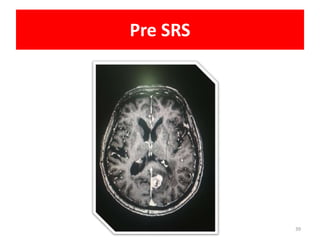

• NAME

• UMR

• PRESENTATION • 70 YEAR FEMALE

• TRIPLE NEGATIVE BREAST CANCER

• POST MRM

• POST RT/CHEMO

• 6 MONTH FOLLOW UP

• PRESENTED WITH HEADACHE AND GIDDINESS

• MRI • 2.2cm x2.2 cm LESION

• LT.OCCIPITAL LOBE

• RING ENHANCEMENT

• NO MASS EFFECT

• NO MID LINE SHIFT

• MINIMAL EDEMA

Pre SRS

• NAME • UMR •PRESENTATION • 70 YEAR FEMALE • TRIPLE NEGATIVE BREAST CANCER • POST MRM • POST RT/CHEMO • 6 MONTH FOLLOW UP • PRESENTED WITH HEADACHE AND GIDDINESS • MRI • 2.2cm x2.2 cm LESION • LT.OCCIPITAL LOBE • RING ENHANCEMENT • NO MASS EFFECT • NO MID LINE SHIFT • MINIMAL EDEMA • PET CT • MULTIPLE LUNG NODULES • BRAIN LESION INCREASED Uptake • SRS • SRS • 18Gy/1# Case details 38